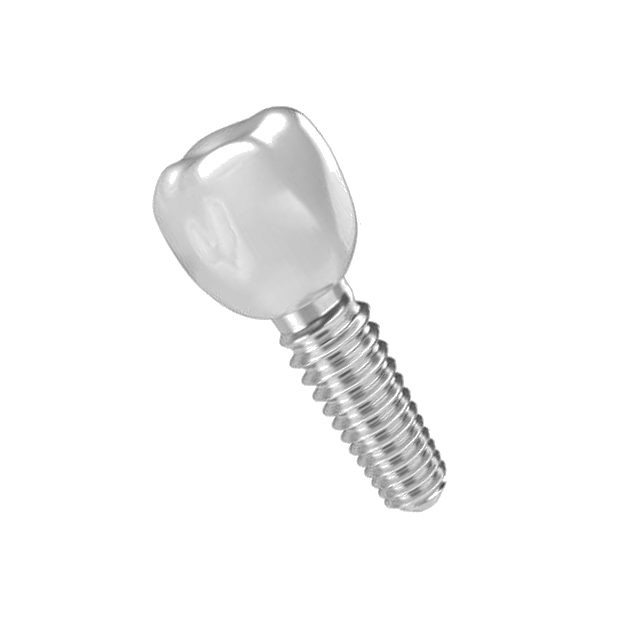

Для імплантації у «Здоровій усмішці» використовують тільки якісні імплантати виробництва Ізраїлю чи Південної Кореї. У нас в клініці ви можете зробити панорамний, КТ чи 3D знімок. За вашим бажанням можемо замовити матеріали зі Швеції чи іншої країни.